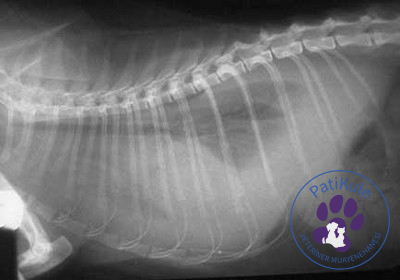

Nörolojik FIP tedavisi için öncelikle teşhis koyulması gerekir ancak hastalığın teşhisi diğer hastalıklara göre zordur. Çünkü FIP başka hastalıklar ile karıştırılabilir. Bu yüzden de PatiKule 7/24 Acil Veteriner gibi uzman klinikten yardım alınması gerekir. Teşhis koyulması için ise birden fazla nokta üzerinde durulur.